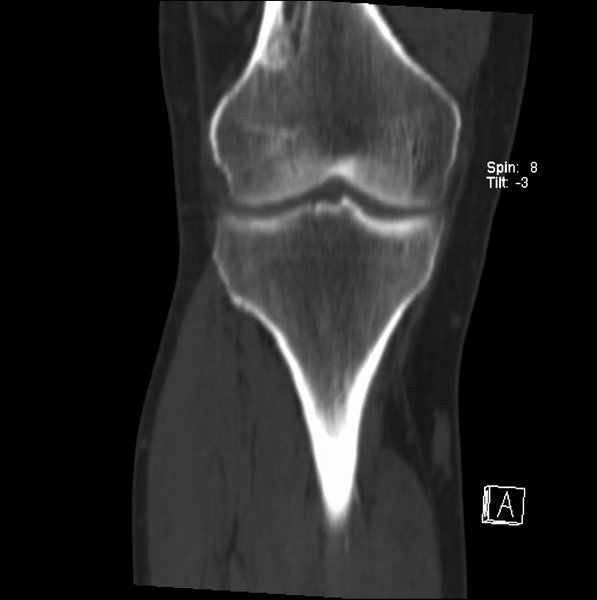

标题: CT21959:骨肿瘤请会诊。

右侧膝关节疼痛一月

男、48

股骨下段、胫骨上段。

1、股骨干骺端病变考虑干骺端纤维性皮质缺损愈后(非骨化性纤维瘤)改变,胫骨近端内生骨瘤(或干骺端纤维性皮质缺损愈后改变);

2、骨关节炎,骨质增生,股骨外侧髁退变性囊肿(关节面软骨下囊肿);

股骨干骺端病变考虑干骺端纤维性皮质缺损愈后(非骨化性纤维瘤)改变,胫骨近端内生骨瘤(或干骺端纤维性皮质缺损愈后改变);

1、股骨干骺端病变考虑干骺端纤维性皮质缺损愈后(非骨化性纤维瘤)改变,胫骨近端内生骨瘤;

股骨干骺端病变考虑非骨化性纤维瘤。

支持非骨化性纤维瘤

非骨化性纤维瘤